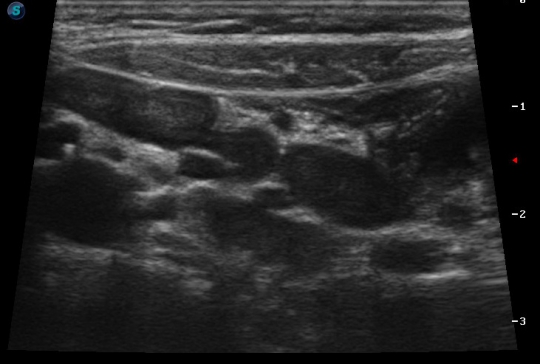

Лимфаденопатия ворот печени по ходу гепатодуоденальной связки. Отсутствие усиления кровотока не в пользу лимфаденита... Было бы интересно знать, какого состояние других лимфоузлов (парааортальных, мезентериальных, ворот селезёнки, периферических...), размеры и структуру печени и селезёнки. Тенденция лимфоузлов к слиянию в "пакет" (очень похоже - слева не один узел, а два слившихся) наводят на нехорошие мысли в плане дифференциальной диагностики (ЛГМ, другие лимфомы...).

Для лимфопролиферативных заболеваний характерно изменение формы, структуры и васкуляризации лимфоузлов (обычно они округлые, гипоэхогенные и гиперваскуляризированные).

Гипоэхогенные образования с четкими неровными контурами, со слабо выраженным центральным эхокомплексом- признаки увеличенных лимфоузлов брюшной полости.